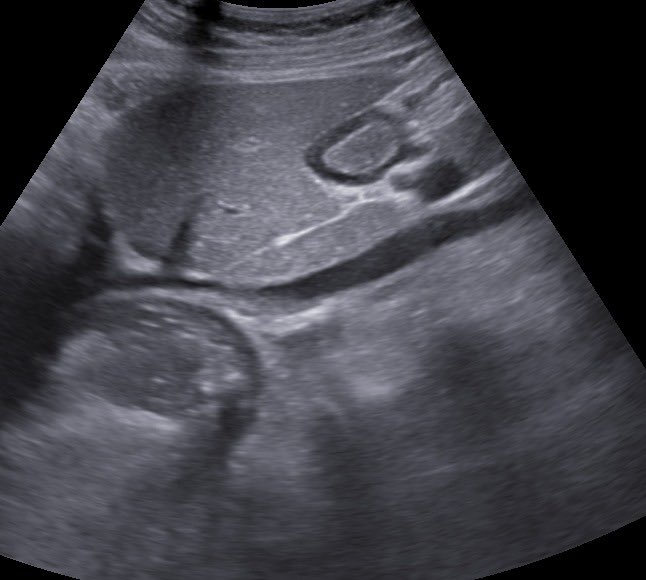

#POCUS

🎅🎄 Quiz:

While doing #gastricultrasound ….you find this ?? What is it ? (CXR as clue) !